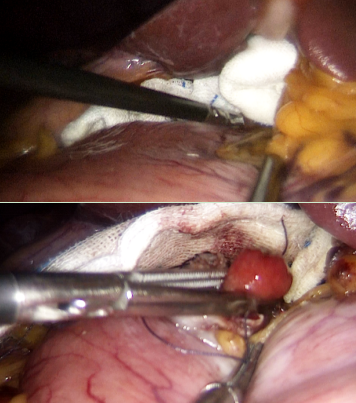

腹腔镜术中肿瘤位置

手术当日,胃肠(肛肠、疝)外科赖苏何副主任医师与消化内科彭洪主治医师携手合作,采用先进的腹腔镜与胃镜双镜联合技术,为患者杨某实施了十二指肠神经内分泌肿瘤切除术。手术过程中,主刀医生们首先通过胃镜精准定位肿瘤位置,确保手术的精确性;随后,利用三孔腹腔镜技术,在腹腔内进行精细操作,将肿瘤完整切除,并巧妙缝合十二指肠球部小弯侧切口。整个手术过程顺利,术后病理证实肿瘤被完整切除,无残留。